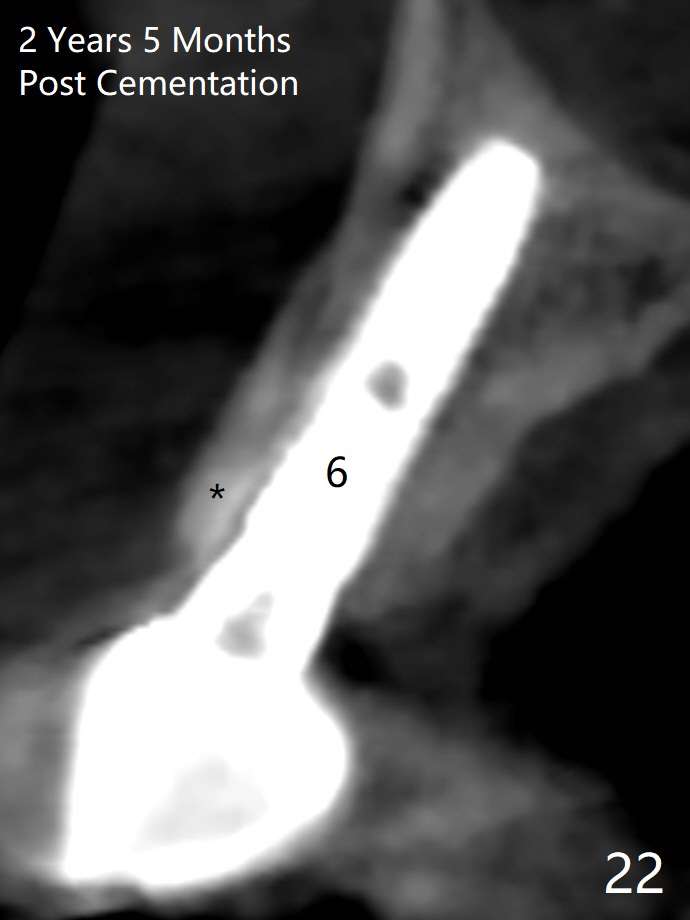

Since the ridge at #7 is ~ 4 mm, a 2.5x14 mm 1-piece implant is placed (Fig.8) after 1.2 mm (Fig.7), and 1.5 mm drills at 12 mm and 2 mm drill at 8 mm.  Later the implant is placed deeper (Fig.10).  There is no bone loss 7 or 12 months postop, respectively (Fig.11,12).  After Diode gingivectomy, there is papillary formation (Fig.13).  No provisional is provided after impression (with the abutment torqued at #6) for oral hygiene.  With access holes at #6 and 7, crowns are bonded with minimal residual cement (Fig.14 <, which is removed later).  There is no hard (Fig.15,16) or soft (Fig.17 *) atrophy 26 months postop, i.e., 13 months post cementation, due to the presence of socket shield (Fig.15 <, as compared to Fig.1).  In fact the tooth #8 has mobility and fremitus (short root/poor crown/root ratio, Fig.16); occlusal adjustment is done 13 months post cementation.  The crown is dislodged 2 years 1 month post cementation; a prefabricated post is being tried in (Fig.18).  There is no atrophy, bone loss or infection at #6 (with socket sheath (*)) or 7 two years 5 months post cementation (Fig.20-27).